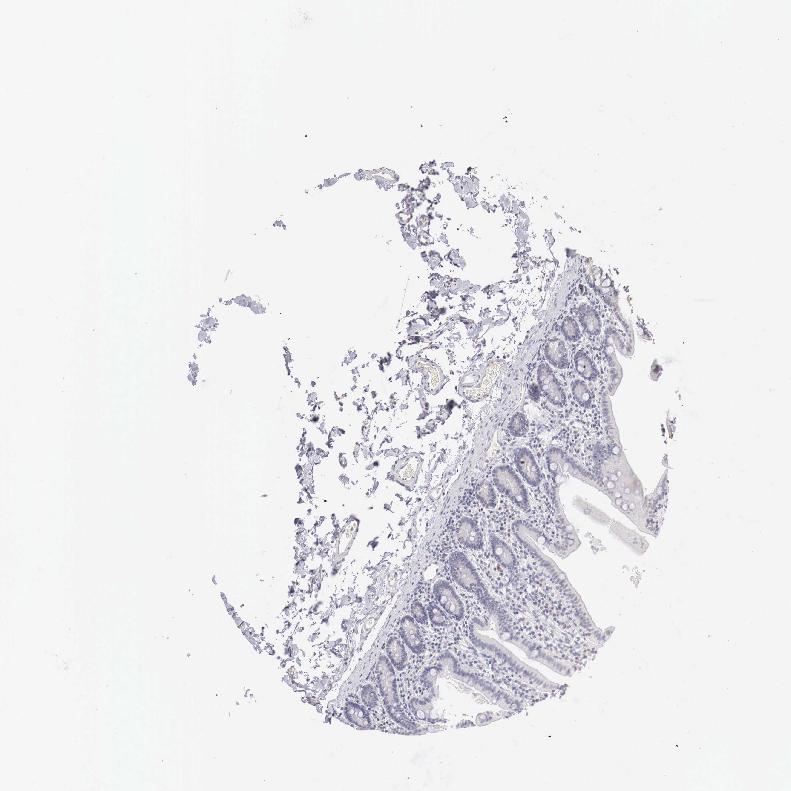

DUODENUM - Antibody stainingi

Antibody staining in the annotated cell types in the current human tissue is reported as not detected, low, medium, or high, based on conventional immunohistochemistry profiling in selected tissues. This score is based on the combination of the staining intensity and fraction of stained cells.

Each image is clickable and will lead to virtual microscopy that enables deeper exploration of all samples and also displays staining intensity scores, fraction scores and subcellular localization as well as patient and tissue information for each sample.

Antibody HPA000289Antibody CAB019435Antibody CAB073410

Glandular cells Not detectedMediumMedium